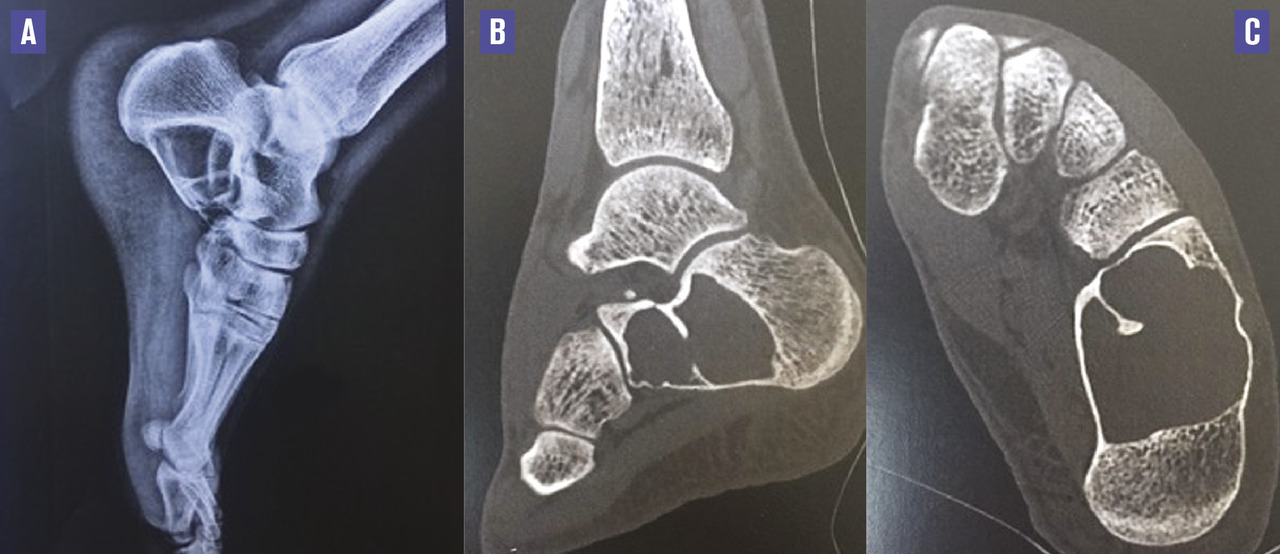

Ce patient de 30 ans consultait à la suite d’une chute sur le talon gauche. L’examen révélait une douleur à la palpation des parties molles en regard du calcanéum, une rougeur et un œdème localisé sans hématome. Une radiographie du pied a permis de découvrir, fortuitement, une vacuité radioclaire du calcanéum, liée à un kyste osseux simple de grande taille, confirmé par un scanner, sans fracture associée (figure).